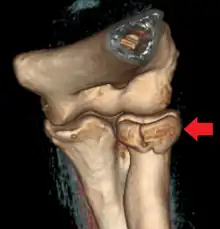

Radial head fracture seen on 3D CT reconstruction

Radial head fractures are diagnosed from an assessment and diagnostic imaging. Assessment may include pain or tenderness at the radial head, bruising, swelling, and a limited range of motion of the elbow.[7] Diagnostic imaging may include ultrasound, plain X-ray, CT scan, and magnetic resonance imaging (MRI).[7][8] A fat pad sign may be present on diagnostic imaging and may indicate a radial head fracture.[9]